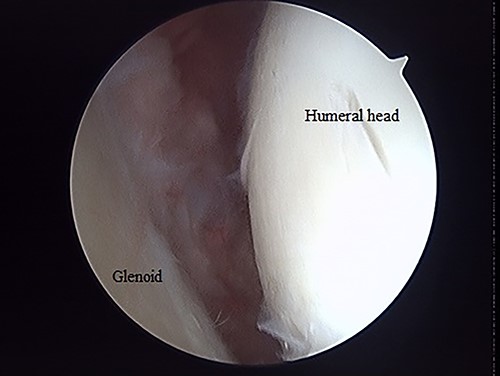

Posterior arthroscopy of the right shoulder joint showing a reduced depressed surface and the Kirschner wire for reduction guide.